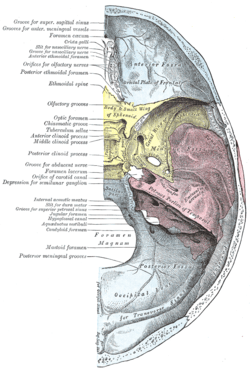

Occipital bone. Inner surface. Jugular process shown in red. | |